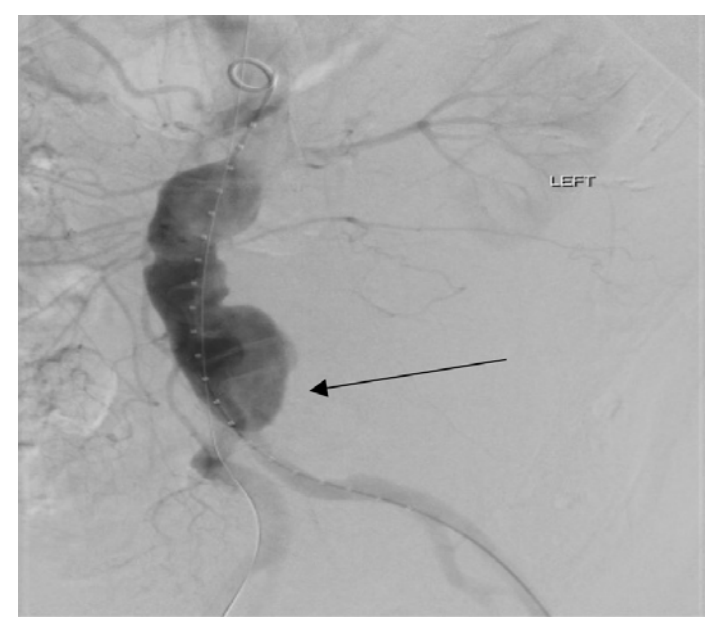

The patient was taken directly to surgery. An intraoperative aortogram revealed a nipple like projection at the distal part of the aorta and this was probably the area where he had ruptured (Figure 1). The patient underwent endoluminal graft placement under local anesthesia.

The postoperative course was uneventful. Since the patient did not get a preoperative CT scan, we decided to do a CT scan prior to his discharge. The CT scan revealed a left perinephric and retroperitoneal hematoma adjacent to prior AAA rupture and an incidental large 7 cm middle 1/3 splenic artery aneurysm (Figure 2), for which the patient underwent coil embolization of the splenic artery aneurysm. Postoperatively, the patient did very well and a repeat CT scan yielded no evidence of splenic infarction or other pathology.